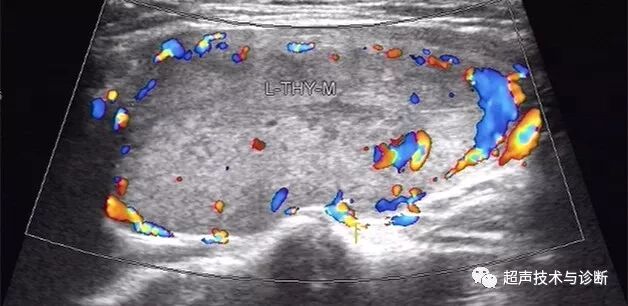

4 CDFI:结节周边声晕处可见环状包绕的血流信号,外周血流多于结节内部血流信号。

(图3-6)甲状腺滤泡型腺瘤,结节内部及周边均可见较丰富血流,周边可见环状血流信号